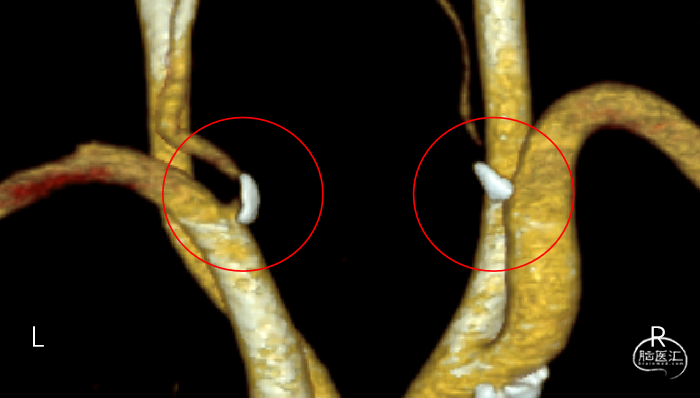

辅助检查(CTA):双侧椎动脉开口重度狭窄,左侧椎动脉为优势动脉,椎动脉颅内段及基底动脉显影良好。

辅助检查(CTA):双侧椎动脉开口重度狭窄。